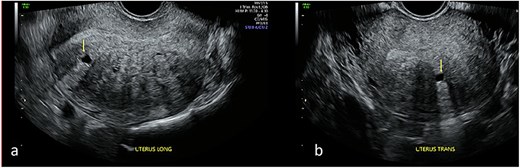

Repeat specialist ultrasound (Fig. 1) identified a right interstitial ectopic pregnancy measuring 27 × 24 × 26 mm, with a decidual reaction, a foetal pole and absent cardiac activity. The gestational sac did not communicate with the endometrial cavity. Diffuse cystic adenomyosis was noted (Fig. 2). Retrospective review indicated that sub-endometrial microcysts had been mistaken for a gestational sac on earlier scans (Fig. 3).

Transabdominal ultrasound of the uterus demonstrating cystic sub-endometrial spaces that were mistaken for a gestational sac in earlier ultrasound scans. The sub-endometrial space is demonstrated in longitudinal (a) and transverse planes (b) and under magnification (c) with a notable absence of decidual reaction around the cystic space.

This case demonstrates how adenomyosis can confound early pregnancy imaging, leading to delayed diagnosis of interstitial ectopic pregnancy. Myometrial cysts and sub-endometrial microcysts—common in adenomyosis—may resemble an early gestational sac, particularly in pregnancies of unknown location. Sub-endometrial microcysts are among the strongest ultrasonographic predictors of adenomyosis [8], and the prevalence is higher among women with subfertility [9]. In this case, adenomyosis-related cystic spaces contributed directly to misinterpretation and delayed recognition of the interstitial pregnancy.